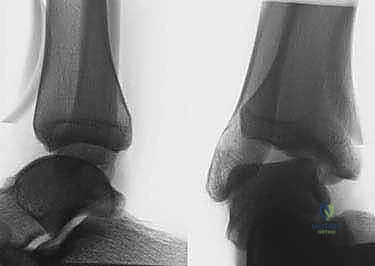

- التقييم السريري الدقيق: يتضمن اختبار الدرج الأمامي (Anterior Drawer Test) لتقييم رباط ATFL، واختبار إمالة الكاحل (Talar Tilt Test) لتقييم رباط CFL.

- الأشعة السينية (X-rays) مع اختبار الإجهاد: صور أشعة عادية لاستبعاد الكسور أو النتوءات العظمية، وصور أثناء الضغط على المفصل لقياس زاوية عدم الاستقرار بدقة.

- الرنين المغناطيسي (MRI): وهو الفحص الأهم لتقييم جودة الأربطة المتبقية، والكشف عن أي إصابات مصاحبة في الغضاريف (Osteochondral Lesions) أو تمزقات في الأوتار الشظوية.